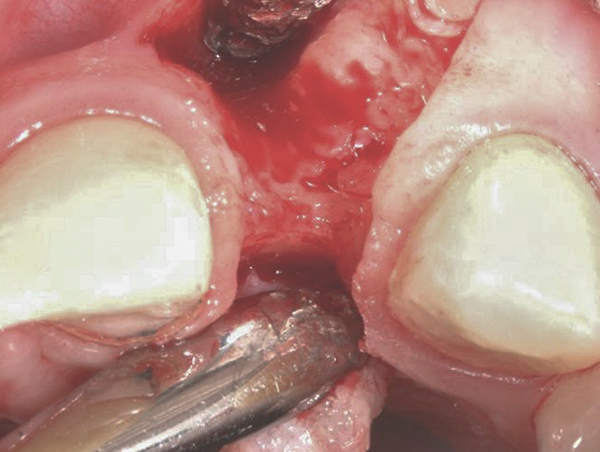

Fig 4. Implant inserted into the ridge, buccal view. There was a large labial concavity. The implant is seen on the buccal and terminates within the alveolar bone.

Figure 4